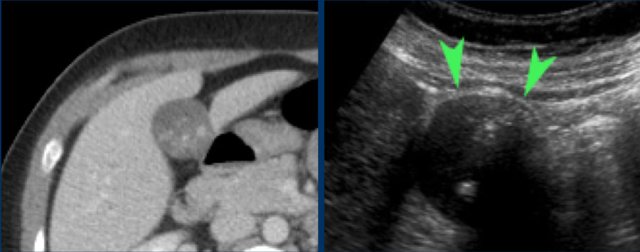

Not infrequently, also on CT scan hydrops of the gallbladder may be identified (fig), but often complementary US is very useful.

Here images of a patient with clinically suspected stomach perforation.

CT shows some stones in a rounded gallbladder.

Complementary US unequivocally demonstrates hydrops (arrowheads).